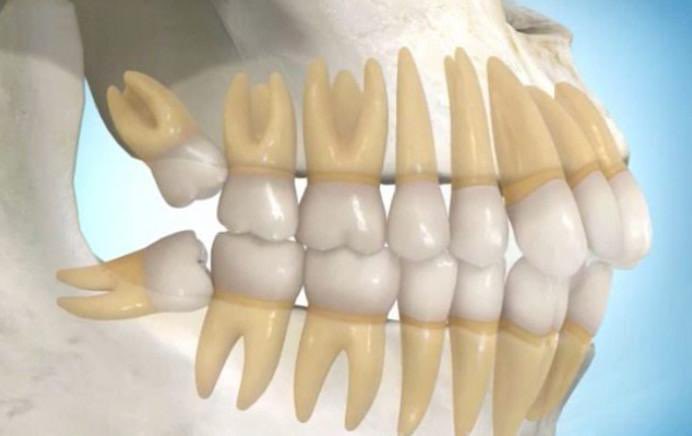

هناك تصور أن ضرس العقل يظهر فى سن متاخرة ليضم جميع الأسنان ويغلق المسافات المفتوحة بين الأضراس فتمنع تراكم الفضلات وعدد ضرس العقل أربعة إثنان بالفك العلوى واثنان بالفك السفلى.

ونظراً لأنها اخر الأسنان التى تظهر بالفم ففى اغلب الاحيان لاتجد لها مكاناً بالفم وبالتالى

إما ان تظل مدفونة فى عظام الفك كلية ، أو تحاول البزوغ جزئياَ، أى يظهر جزء منها بالفم والباقى مدفوناَ بعظام الفك .